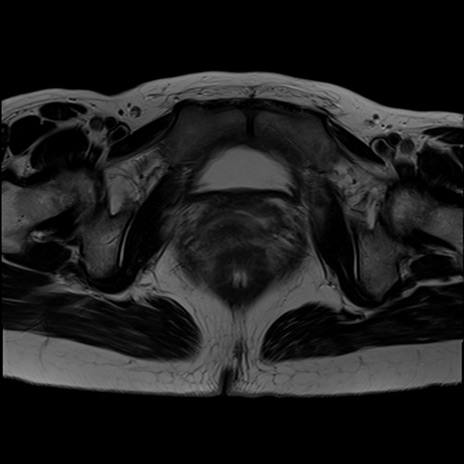

症例39 T2WI(横断像)

MRI(4日後)